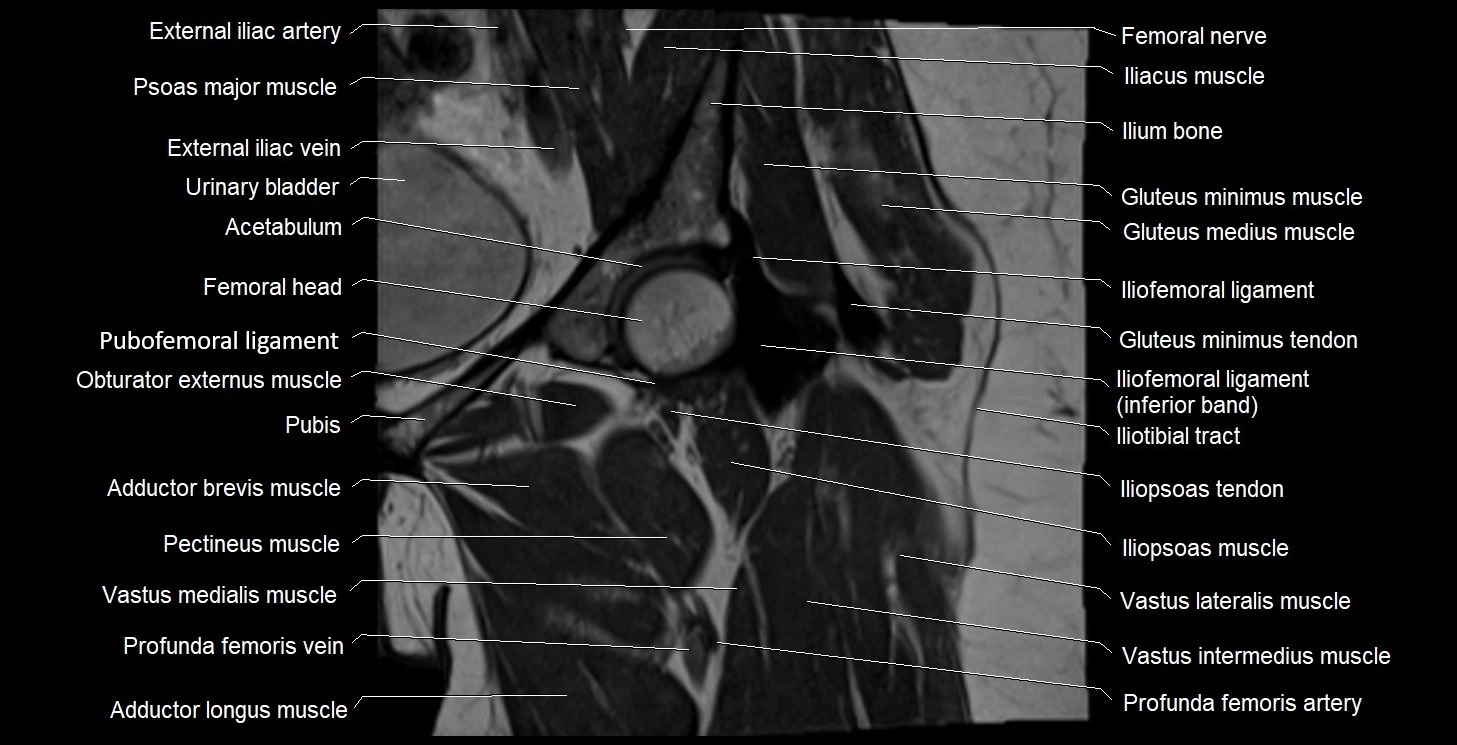

- External iliac artery

- External iliac vein

- Femoral nerve

- Gluteus minimus muscle

- Gluteus minimus tendon

- Greater trochanter

- Head of femur

- Iliofemoral Ligament inferior band (vertical band, medial band)

- Iliofemoral Ligament superior band (transverse band, lateral band)

- Iliofemoral ligament

- Iliopsoas muscle

- Iliopsoas tendon

- Iliotibial tract

- Ilium bone

- Obturator externus muscle

- Pectineus muscle

- Psoas major muscle

- Pubofemoral ligament

- Urinary bladder

- Vastus intermedius muscle

- Vastus lateralis muscle

- Vastus medialis muscle